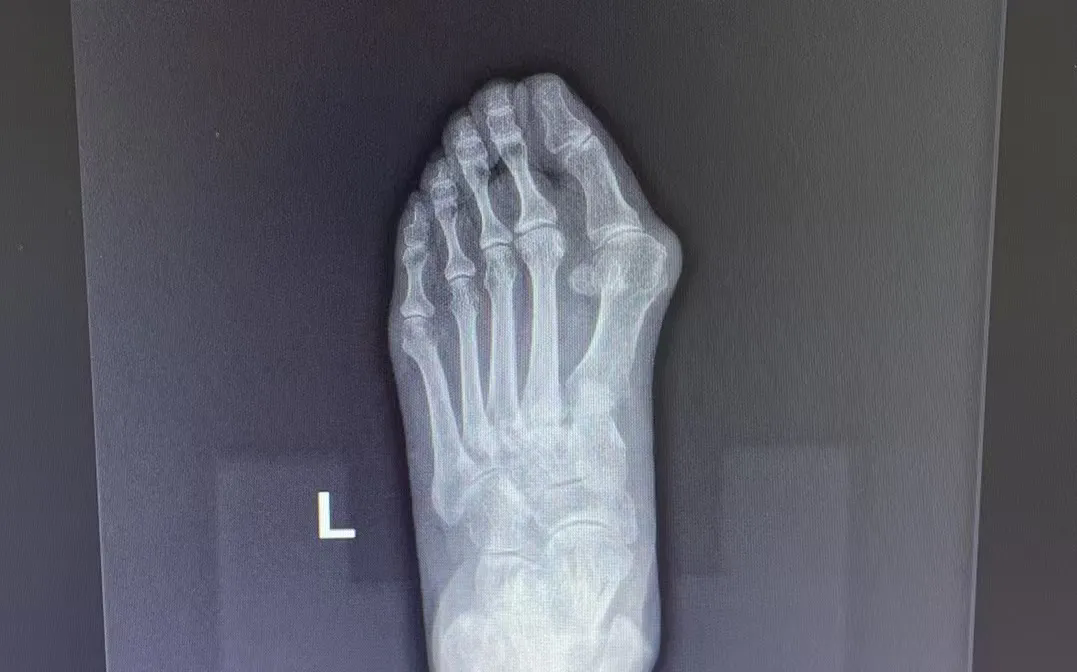

拇指外翻

這一復(fù)雜的解剖畸形

不僅影響美觀

更會(huì)帶來(lái)紅腫疼痛、關(guān)節(jié)炎等癥狀

拇指外翻的成因

?長(zhǎng)期穿著高跟鞋或前頭過(guò)窄的鞋子,會(huì)加劇足部壓力,導(dǎo)致拇趾外翻畸形。

?風(fēng)濕性疾病也可能引發(fā)足部關(guān)節(jié)的炎癥,進(jìn)一步加重拇指外翻的癥狀。